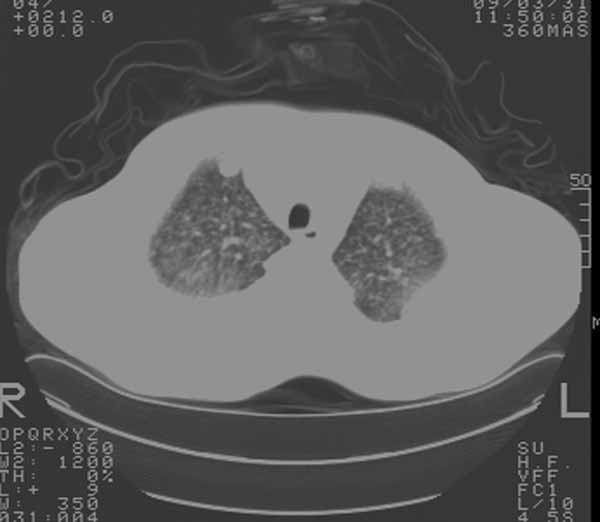

以下是引用余辉在2009-3-31 18:43:00的发言:[br]肺水肿,双侧心腔积液,心包积液,心影增大,疑似心衰

以下是引用wangyong1977在2009-3-31 20:46:00的发言:[br]肺水肿,双侧胸腔积液,心包积液,心影增大,疑似心衰 [br]

以下是引用宇宙ct在2009-3-31 18:57:00的发言:[br]肺水肿,双侧心腔积液,心包积液,心影增大,疑似心衰 [br] [br]